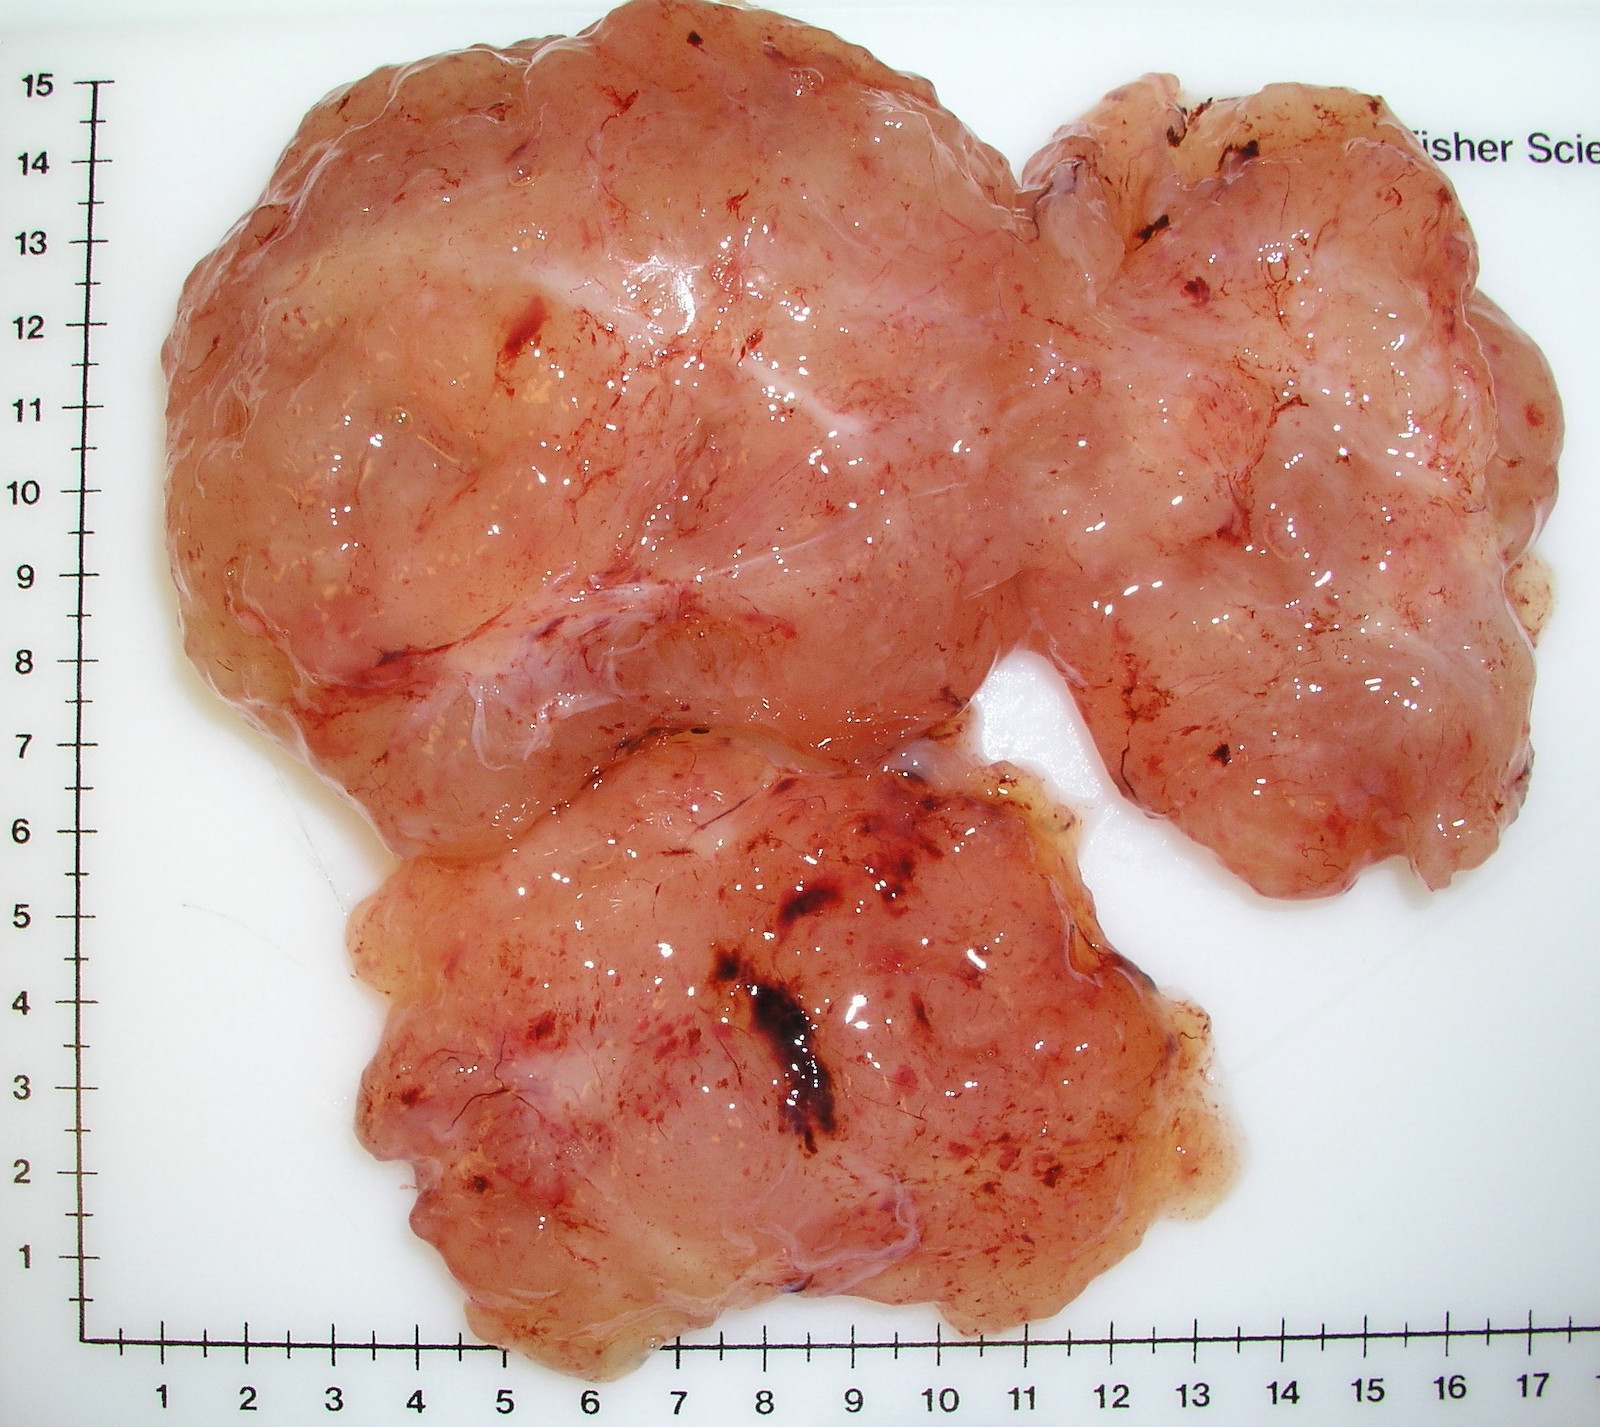

Gross description

- Often large (median ~9 cm), well circumscribed, fibromyxoid cut surface, may be grossly infiltrative

Gross images